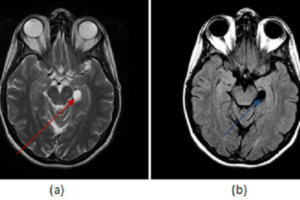

Choroidal Fissure Cyst

A number of pathological processes affect the limbic system. Patients with longstanding temporal lobe seizures can develop mesial temporal sclerosis, a condition characterized by atrophy of the hippocampus. Neoplasms, both benign and... Read more »